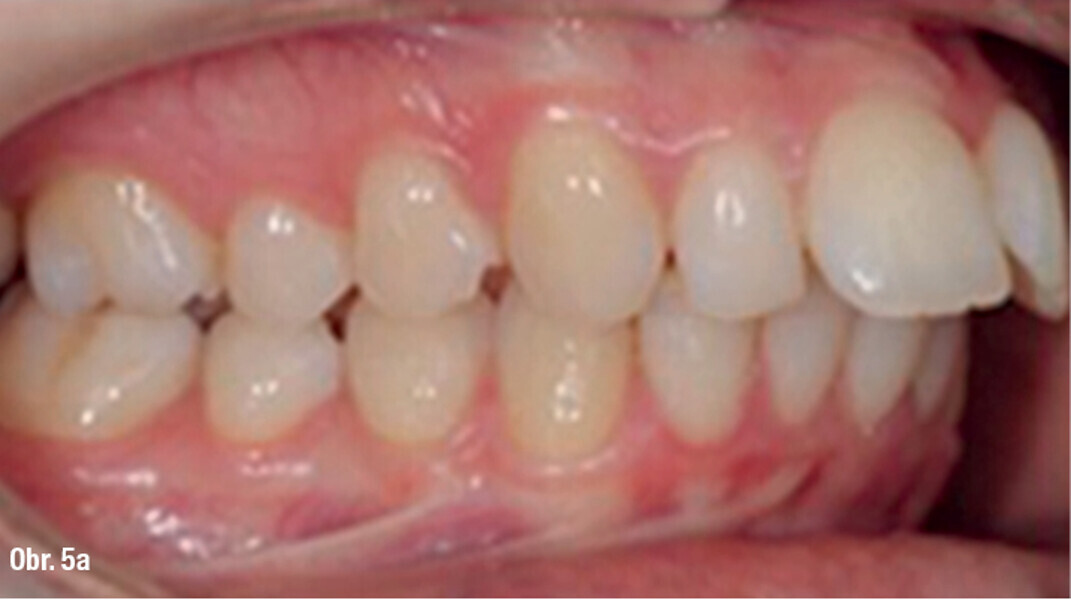

Distalizace horních molárů pomocí alignerů a cyklických sil